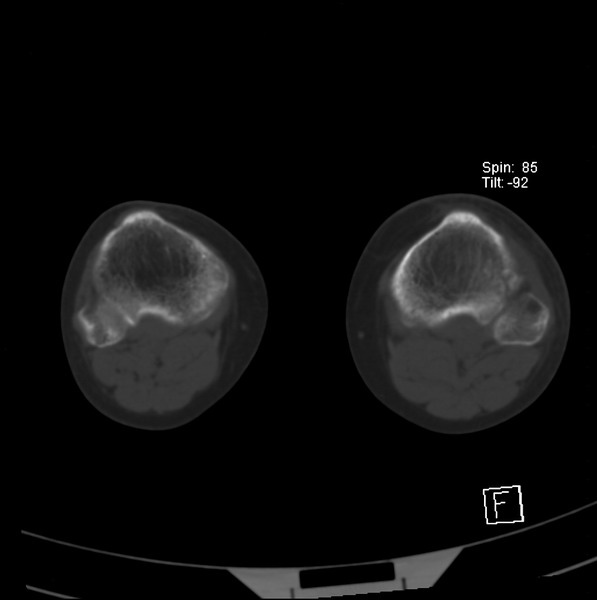

标题: CT21917:右腓骨小头是否骨软骨瘤? [打印本页]

标题: CT21917:右腓骨小头是否骨软骨瘤?

女、43.

不是骨软骨瘤,“牵拽征”,正常变异。有平片吗?

正常变异,“牵拽征”,比目鱼肌牵拽.

比目鱼肌附着点